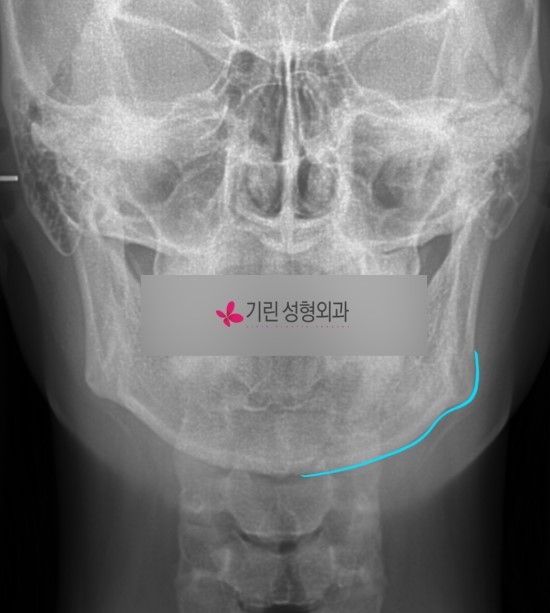

아래는 사각턱수술 전과 후의 엑스레이로 귀밑사각부터 턱 끝까지 절골한 경우입니다.

수술전

수술후

앞턱이 뭉툭하고 U라인으로 넓어도 티절골수술 없이 턱끝까지 브이라인이 가능하기 때문에